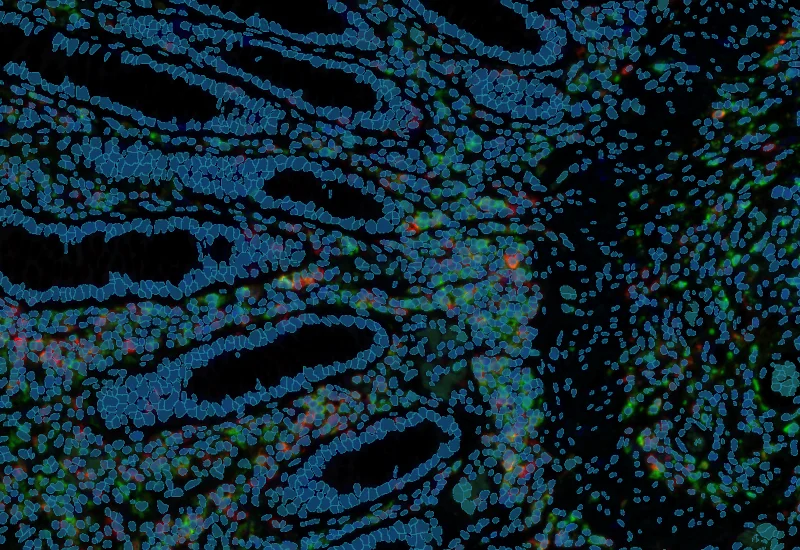

The IF 3 App provides single cell based co-expression analysis for three IF markers. It segments cells into nucleus, and/or perinuclear area and/or cytoplasm. Each segmented cell compartment is measured for up to 20 intensity, statistic and morphometric parameters which can be displayed in scattergrams and histograms and exported.

Co-Expression